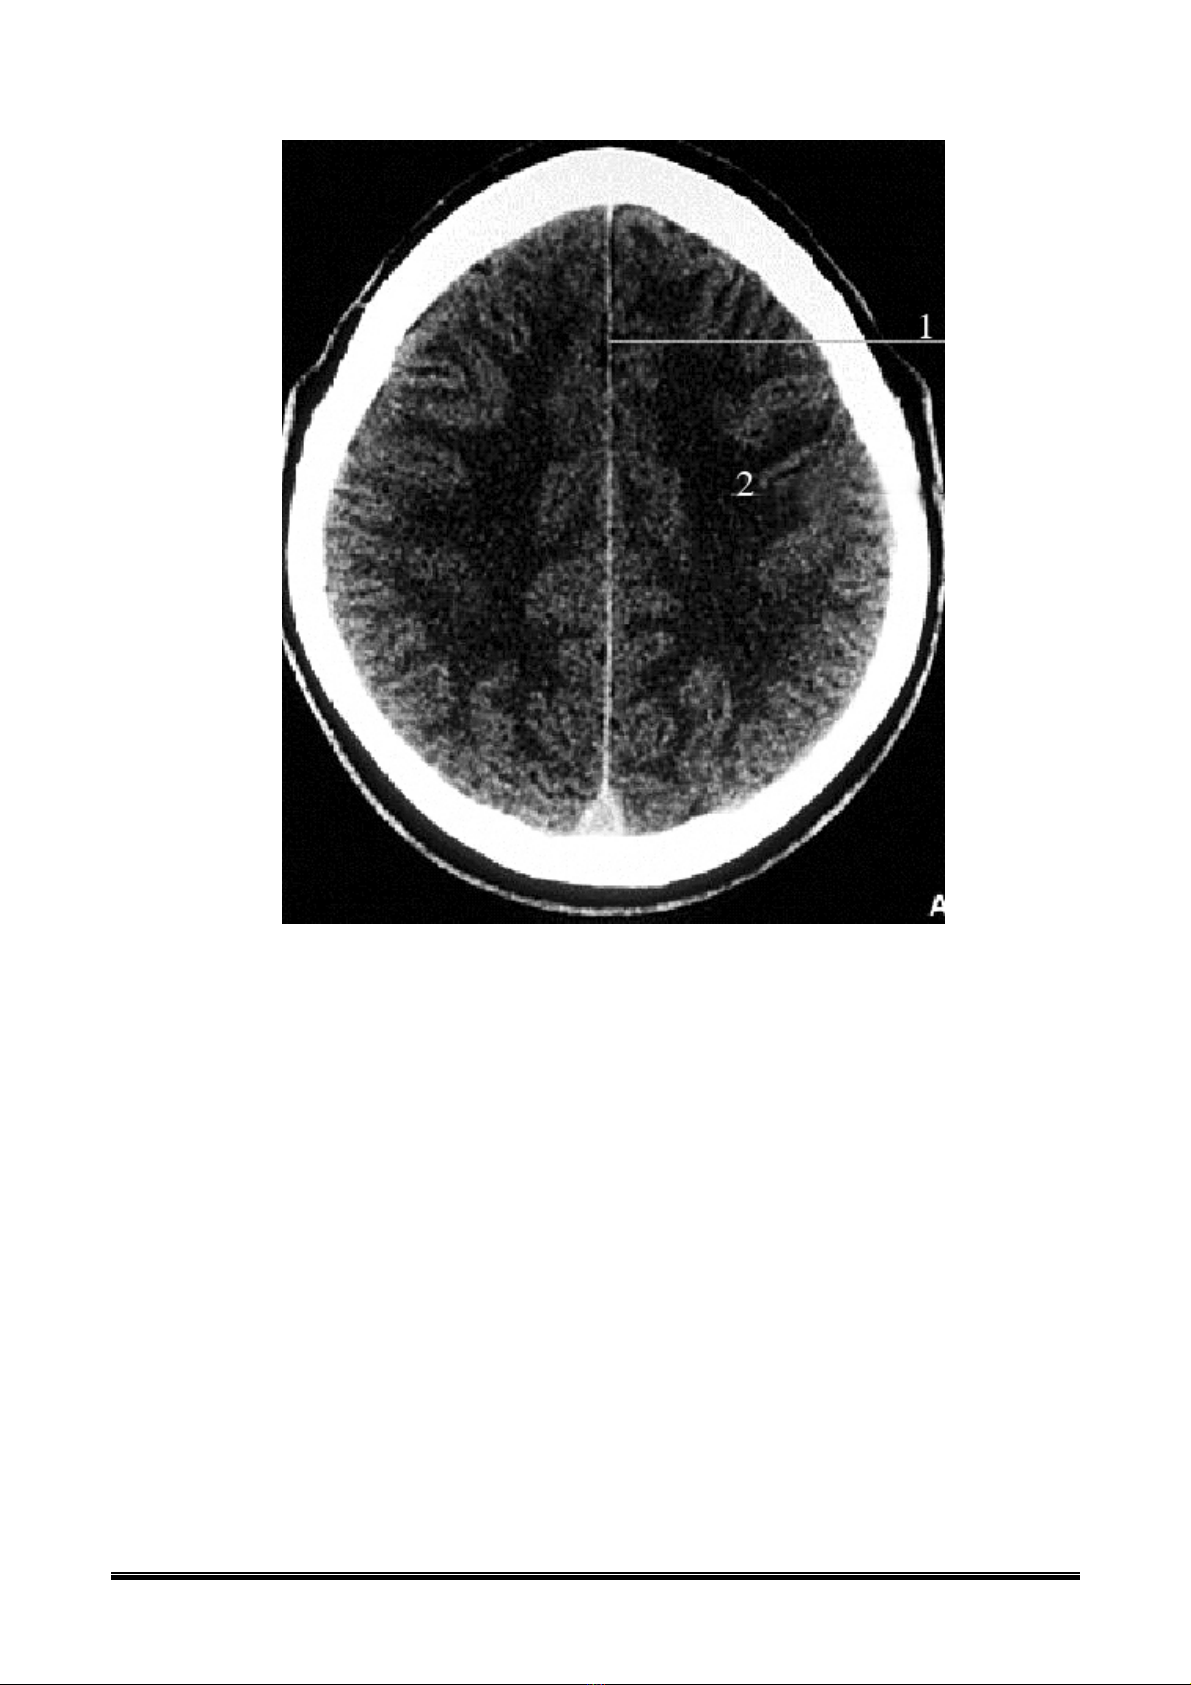

1: LiÒm n·o

2: Trung t©m bÇu dôc